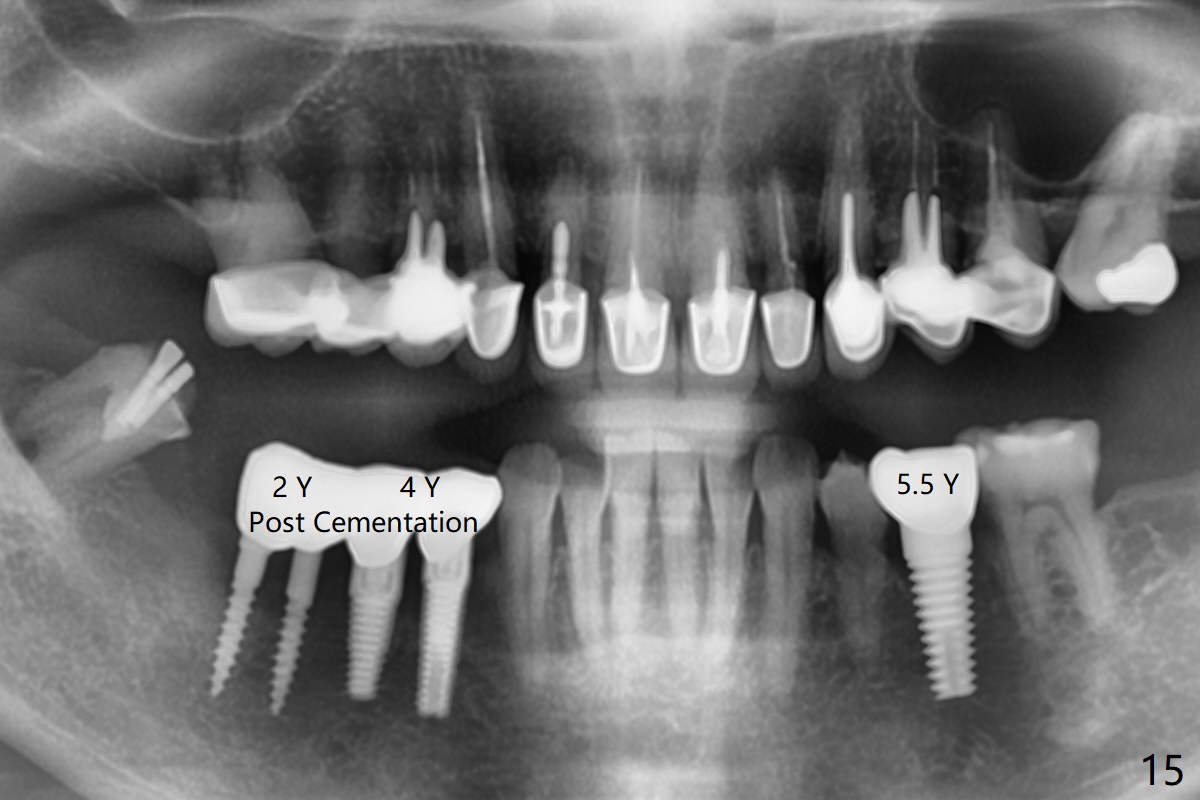

The edentulous ridge at #30 is narrow (Fig.1). After ridge reduction, osteotomy is initiated with 1.2 mm drill for 10 mm; the mesial osteotomy is to be changed (Fig.2 red line). Using a 1.2 mm drill placed in the distal osteotomy (Fig.3 D), the mesial osteotomy changes in trajectory with subsequent placement of a 2.5x10(4) mm 1-piece implant. Since the mesial implant is high in occlusion, the cuff of the distal implant is changed to be 2 mm (Fig.4 (shorter black line)). Panoramic X-ray is taken to show no violation of the Inferior Alveolar Canal (Fig.5 red dashed line). These two 1-piece implants are slightly lingually placed (Fig.6). The crestal bone around the implants resorbs without thread exposure 5 months postop (Fig.7). Impression is taken for a splinted crown (Fig.8-12). There is no metal show around the 2.5 mm 1-piece implants 6 months postop (advantage) vs. that at #28 and 29 (Fig.13). Bitewing is taken post cementation to determine whether residual cement is present (Fig.14). There is periodic swelling and pain in the lower right quadrant 2 years post cementation (Fig.15). In fact periimplantitis appears to have developed at #28 (Fig.16) with loss of the buccal bone (Fig.17,18). The buccal bone loss is less at #29 (Fig.19) and #20 (Fig.23) and no at #30 mesial and distal implants (Fig.20,21). A much smaller implant will be placed lingually at #28 immediate (Fig.24,25).